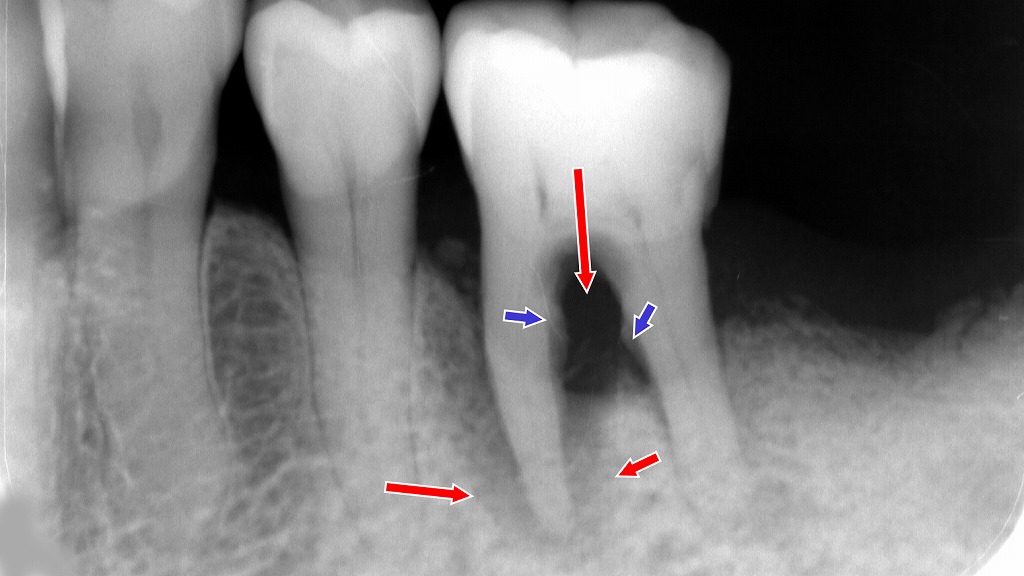

📸 症例:重度歯周病による歯石露出

- 歯茎の炎症と腫れ

→ 歯茎が丸く腫れており、歯周病による炎症が進行中。 - 歯茎の裂開と歯石の露出

→ 歯茎の裂け目から、黒い歯石が歯の表面に出てきている状態。 - レントゲン所見:歯槽骨の破壊

→ 歯周病による影響で、歯を支える骨がかなり失われていることが確認されました。

このレントゲンは、重度歯周病が進行した部位に特徴的な 縁下歯石(青い矢印) と、高度な歯槽骨吸収(赤い矢印) がはっきりと読み取れる症例です。